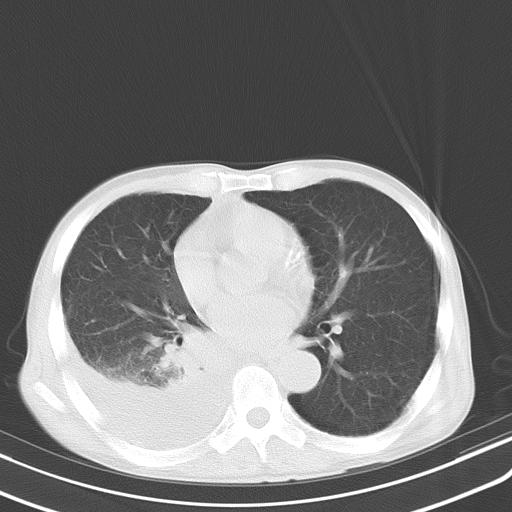

男性 75  咳嗽 一周前发热最高达39

右肺继发型tb并右侧tb性胸腔炎,右侧胸腔大量积液并右下肺膨胀不全,慢支肺气肿、多发肺大泡。建议抽胸水实验室检查并复查排除恶性在占位。

右上肺继发型肺结核,右胸腔中等量积液。

左上肺大泡。

结核的基础上有纵隔淋巴结肿大,右侧有胸水,但右侧纵隔反而窄,说明有肺有不张。

再就是右下肺有块影,和不张混合,还是不能除外肺癌。

补充材料,患者2月份ct片大致正常,双侧胸腔积液,2月份抽胸水未发现ca细胞,现患者发热,痰多,各气管通畅,

1)右肺继发型肺结核。2)左肺胸膜下多发性肺大泡。3)右侧胸腔积液。